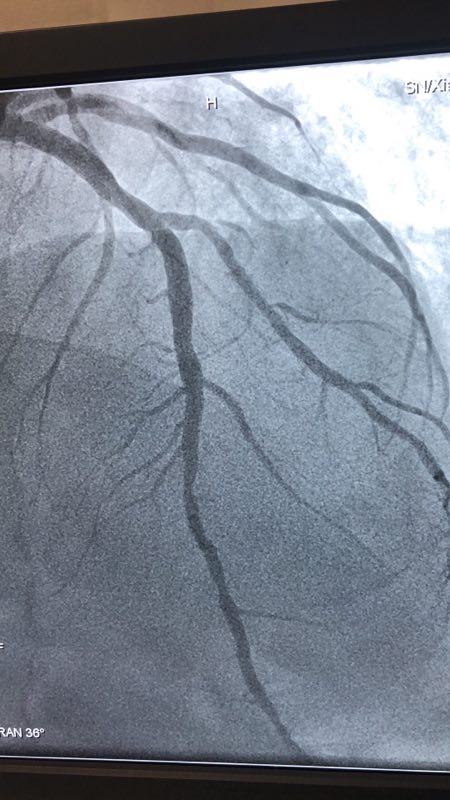

此例患者,男性,56岁,11年前因心绞痛在西京成人导航 行冠状动脉造影检查后于D1对角支置入1枚支架治疗。术后患者口服“阿司匹林肠溶片、氯吡格雷、阿托伐他汀”等药物治疗1年后自行停药,并有长期大量吸烟史。2018年12月24日患者突发胸痛、胸闷,急来成人导航就诊。急诊行冠状动脉造影检查提示D1对角支原支架内再狭窄70%-90%。急救中心主任张誉洋副主任医师考虑到第一对角支管径较小,于原支架内再次置入支架引起再狭窄的风险极大,遂建议应用药物涂层球囊扩张术治疗D1对角支原支架内狭窄。与患者充分沟通后,于12月27日行冠脉药物涂层球囊PTCA术治疗,造影显示血管开通情况良好,术后患者症状明显改善。